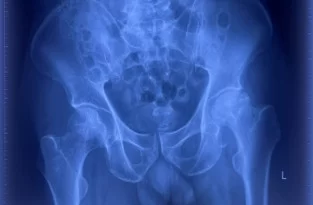

Phẫu thuật thay khớp háng bán phần hay tạo hình đầu gần xương đùi một phần là thủ thuật chỉnh hình dùng để điều trị cho một số trường hợp gãy cổ xương đùi. Trong đó, chỏm xương đùi sẽ được cắt bỏ và thay thế bằng các bộ phận có chất liệu như: kim loại, titanium, nhôm, cobalt hoặc nhựa rất cứng…

Phương pháp phẫu thuật này thường được chỉ định cho những trường hợp gãy cổ xương đùi di lệch nhiều trên bệnh nhân cao tuổi hoặc người không đảm bảo sức khỏe để thực hiện các ca mổ dài và phức tạp

Bên cạnh đó, một trong những trường hợp phổ biến được bác sĩ chỉ định thay khớp háng bán phần chính là gãy cổ xương đùi. Tình trạng này rất thường xảy ra ở người Việt. Trong đó, 80% ca thay khớp háng bán phần là do gãy cổ xương đùi ở người lớn tuổi.